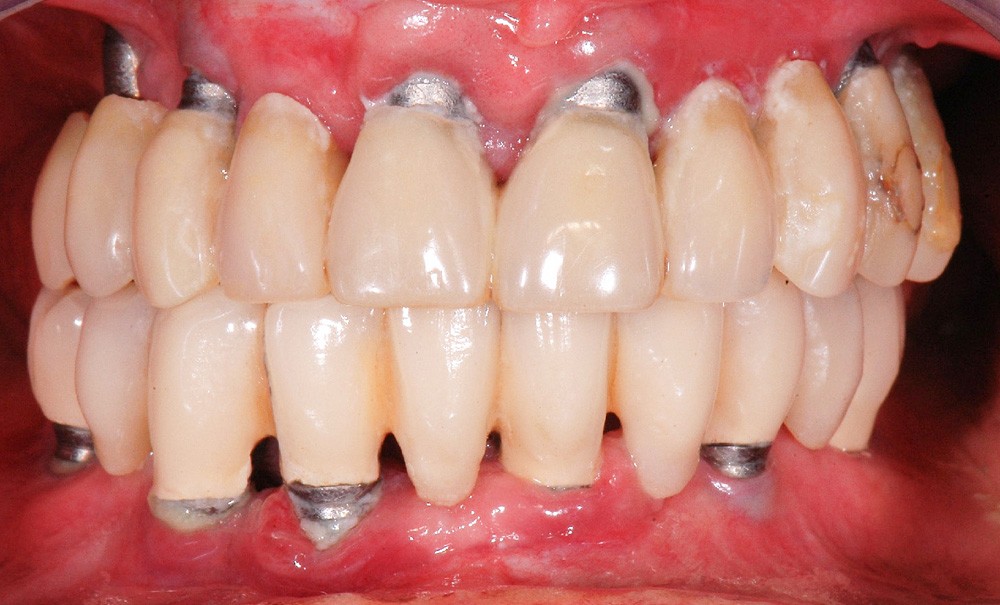

La péri-implantite

La plaque bactérienne (biofilm) pénètre et envahit les tissus muqueux autour des implants dentaires (fig. 3). S’installent une inflammation de la muqueuse péri-implantaire et la perte progressive et asynchrone du tissu osseux [4]. La péri-implantite survient au cours des premières années de mise en fonction de l’implant [4] et en l’absence de traitement, la maladie progresse (fig. 4) de manière non linéaire et rapide [4, 7].